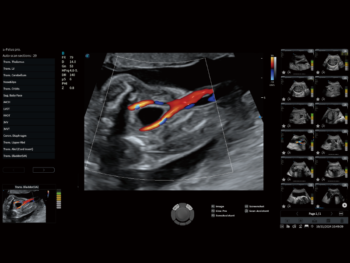

S-Fetus 5.0

Жирэмсний хэвлийд стандарт үзлэг, хэмжилтийг автоматжуулсан иж бүрэн шийдэл юм. Зөвхөн нэг товшилтоор жирэмсний 29 стандарт дүрсийг ухаалаг байдлаар таньж, 13 төрлийн биометрийн хэмжилтийг өндөр нарийвчлалтайгаар автоматаар гаргадаг. Энэ нь эмч нарт ажлыг хялбаршуулж, үр дүнтэй, найдвартай оношлогоо хийх боломжийг олгодог.